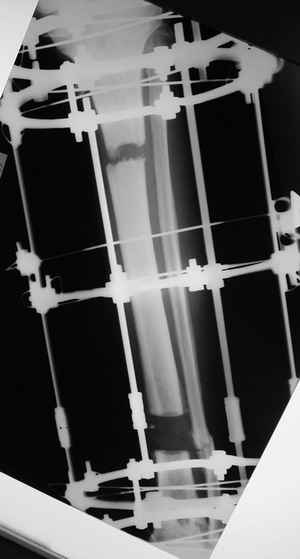

Итак - удалили стержень, воспалительный процесс к тому моменту купирован, наложили кастовую повязку и в течение 3 месяцев на контрольных рентгенограммах - признаки консолидации. Уже в сентябре, т.е черз 5 месяцев после нагноения пациент вернувшиь с подвождной охоты привез здорового сазана - основная жалоба - ноги побаливают после длительного лпаваня в ластах. Прилагаю снимки через год после удаления стержня. Вот такая, на этот раз счастливая казуистика.